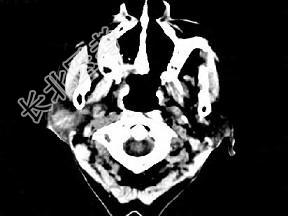

- 单项选择题女,72岁, 六年前于右面颊部扪及一包块,缓慢增大, 其表面较光滑,CT如图所示, 该病例应诊断为 ( )

A、Worthin瘤

B、腮腺混合瘤

C、颈部神经纤维瘤

D、颈部淋巴瘤

E、小唾液腺瘤